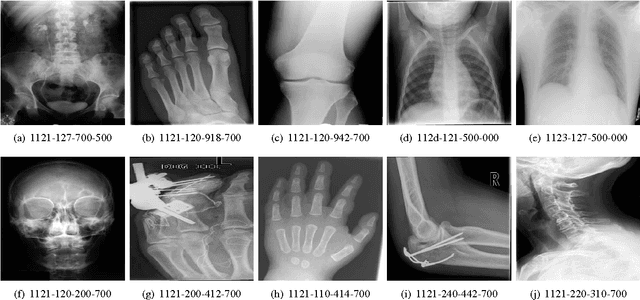

Good results on image classification and retrieval using support vector machines (SVM) with local binary patterns (LBPs) as features have been extensively reported in the literature where an entire image is retrieved or classified. In contrast, in medical imaging, not all parts of the image may be equally significant or relevant to the image retrieval application at hand. For instance, in lung x-ray image, the lung region may contain a tumour, hence being highly significant whereas the surrounding area does not contain significant information from medical diagnosis perspective. In this paper, we propose to detect salient regions of images during training and fold the data to reduce the effect of irrelevant regions. As a result, smaller image areas will be used for LBP features calculation and consequently classification by SVM. We use IRMA 2009 dataset with 14,410 x-ray images to verify the performance of the proposed approach. The results demonstrate the benefits of saliency-based folding approach that delivers comparable classification accuracies with state-of-the-art but exhibits lower computational cost and storage requirements, factors highly important for big data analytics.